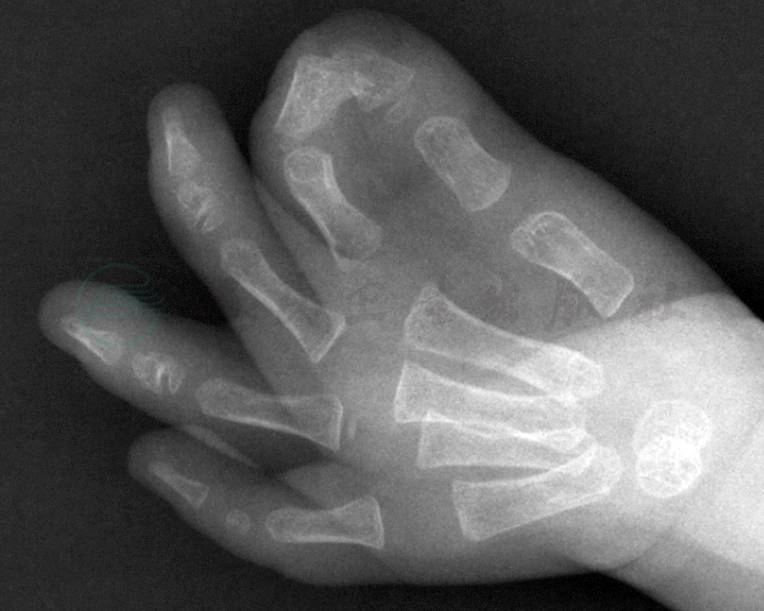

并指畸形表现为两个或两个以上手指的组织结构完全性或不完全性相连,可单纯的皮肤并连(图1),也可伴有指骨或掌骨融合,并合并各种形态的指甲畸形(图2),因而不能用一种简单的表现形式来描述。临床上常常根据并指畸形的形态、部位、组织结构以及伴随畸形,采用不同的分型方法来描述。

图2拇示指并指畸形伴骨性融合